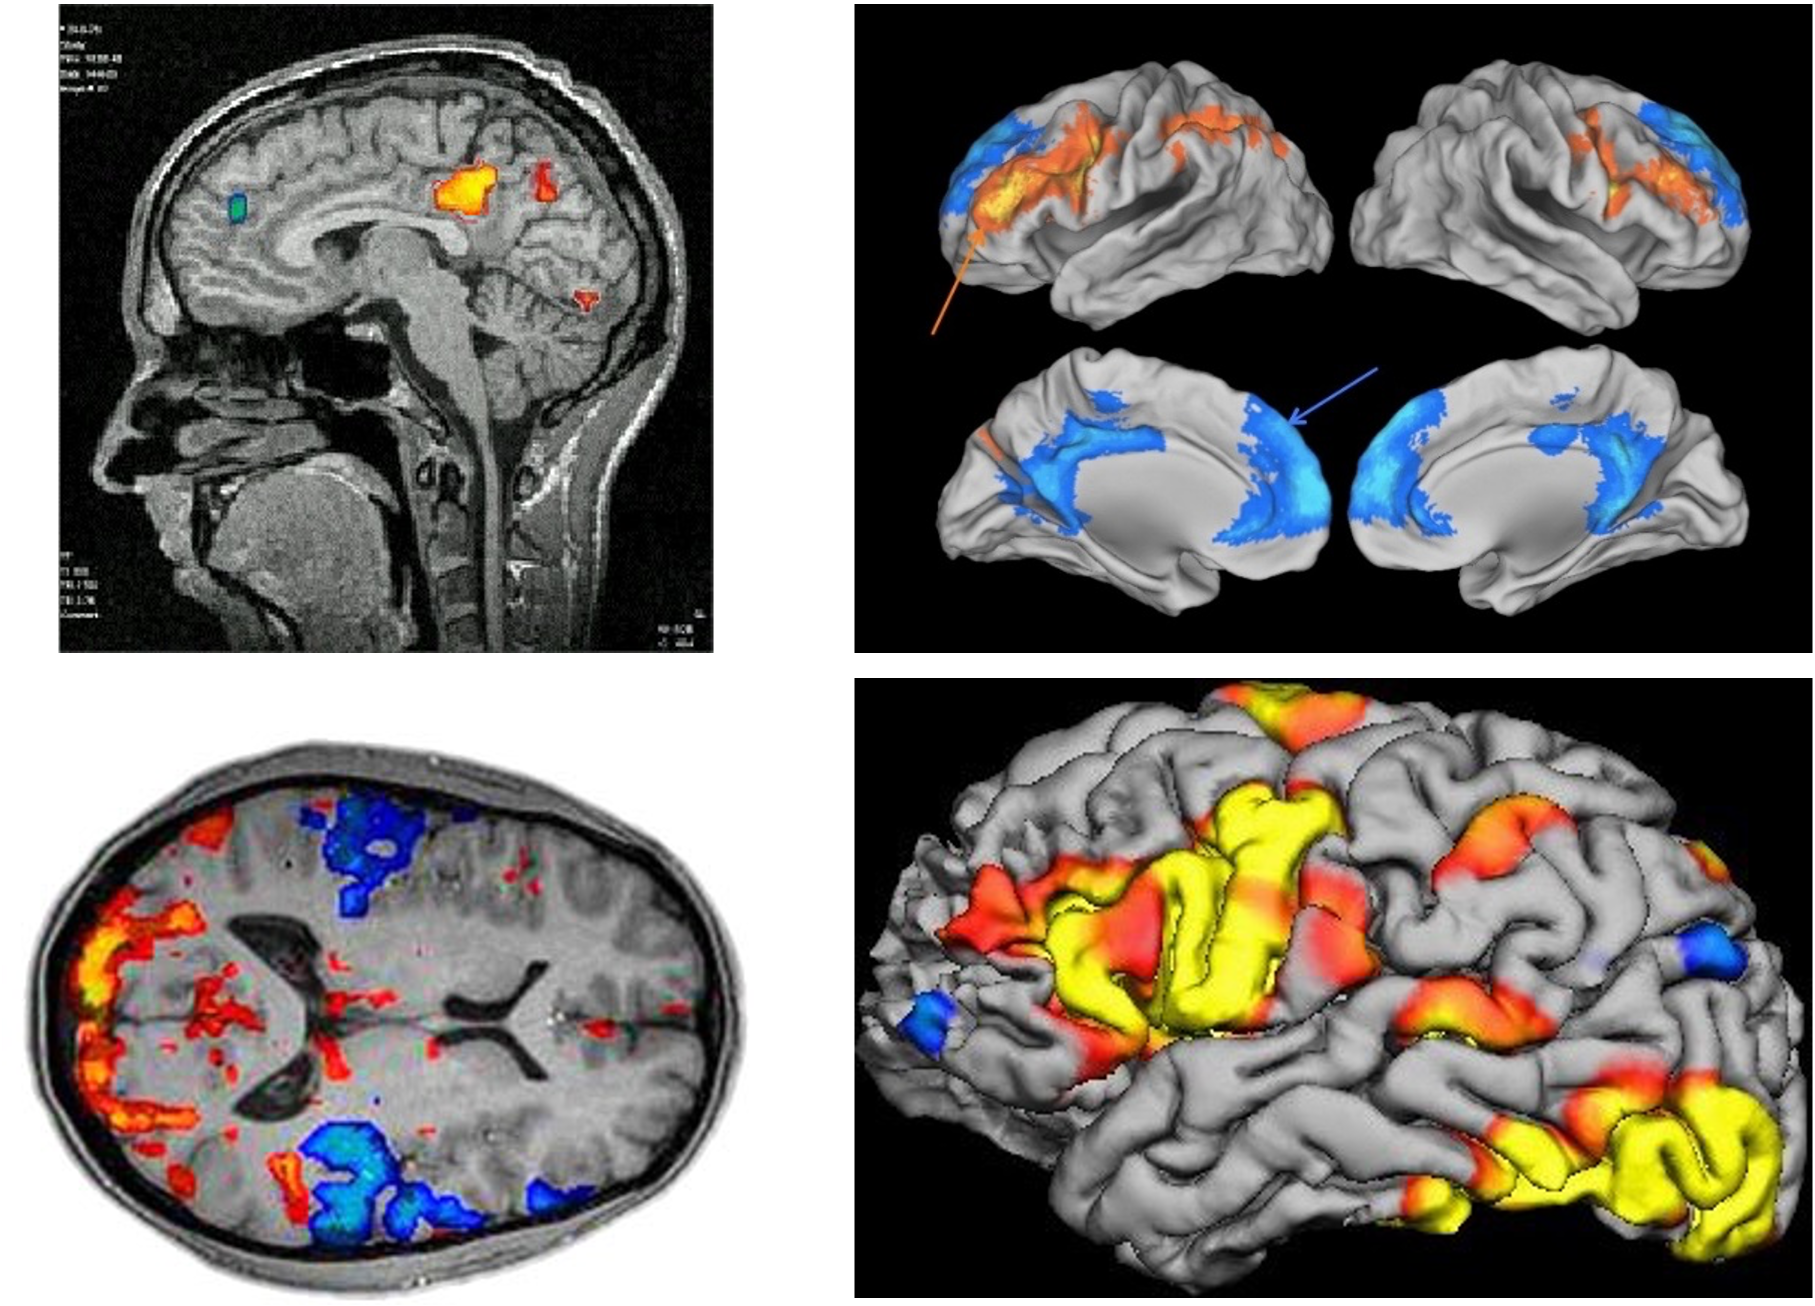

Where are the areas more active in Condition A than in Condition B?

Overview of the fMRI method.

How to interpret fMRI data.